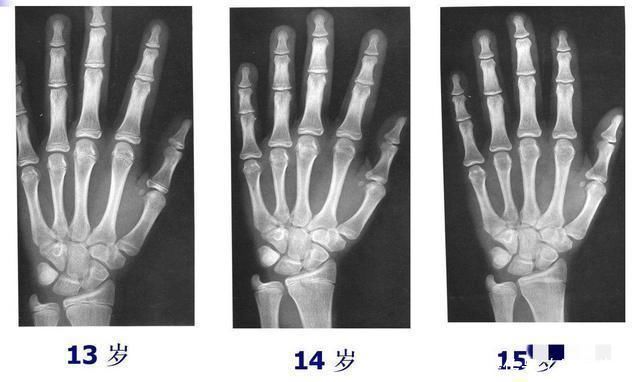

2、测骨龄这种方式较为准确科学,可到正规的医院给孩子拍个骨龄片子,医生会告诉你是否发育存在滞后的问题。

毕竟现在的孩子生活水平高,普遍存在早熟问题,若骨龄超前,也会导致身高发育受限。